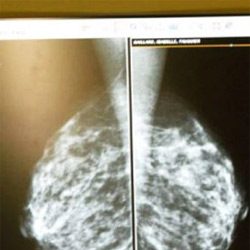

Proposed breast cancer screening guidelines would increase deaths: Experts

Experts has warned against the proposed breast cancer screening guidelines as they shall increase deaths. The breast cancer screening guidelines proposed yesterday by the United States Preventive Services Task Force (USPSTF) would result in thousands of additional and unnecessary breast cancer deaths each year, according to radiologists at Loyola University Health … [Read more...]